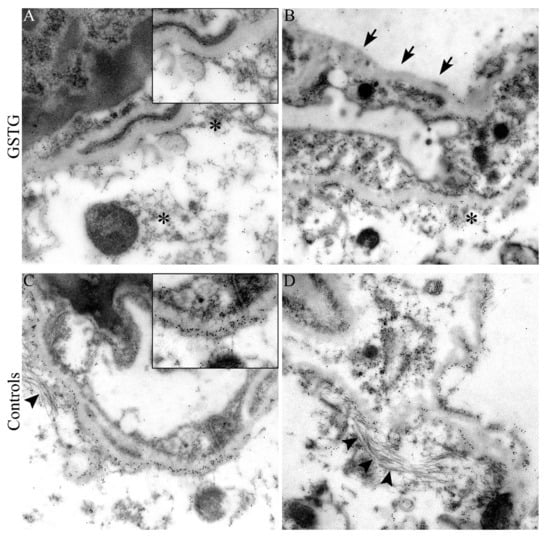

2.3. Astrocyte Phenotype

4.6. Immunoelectron Microscopy